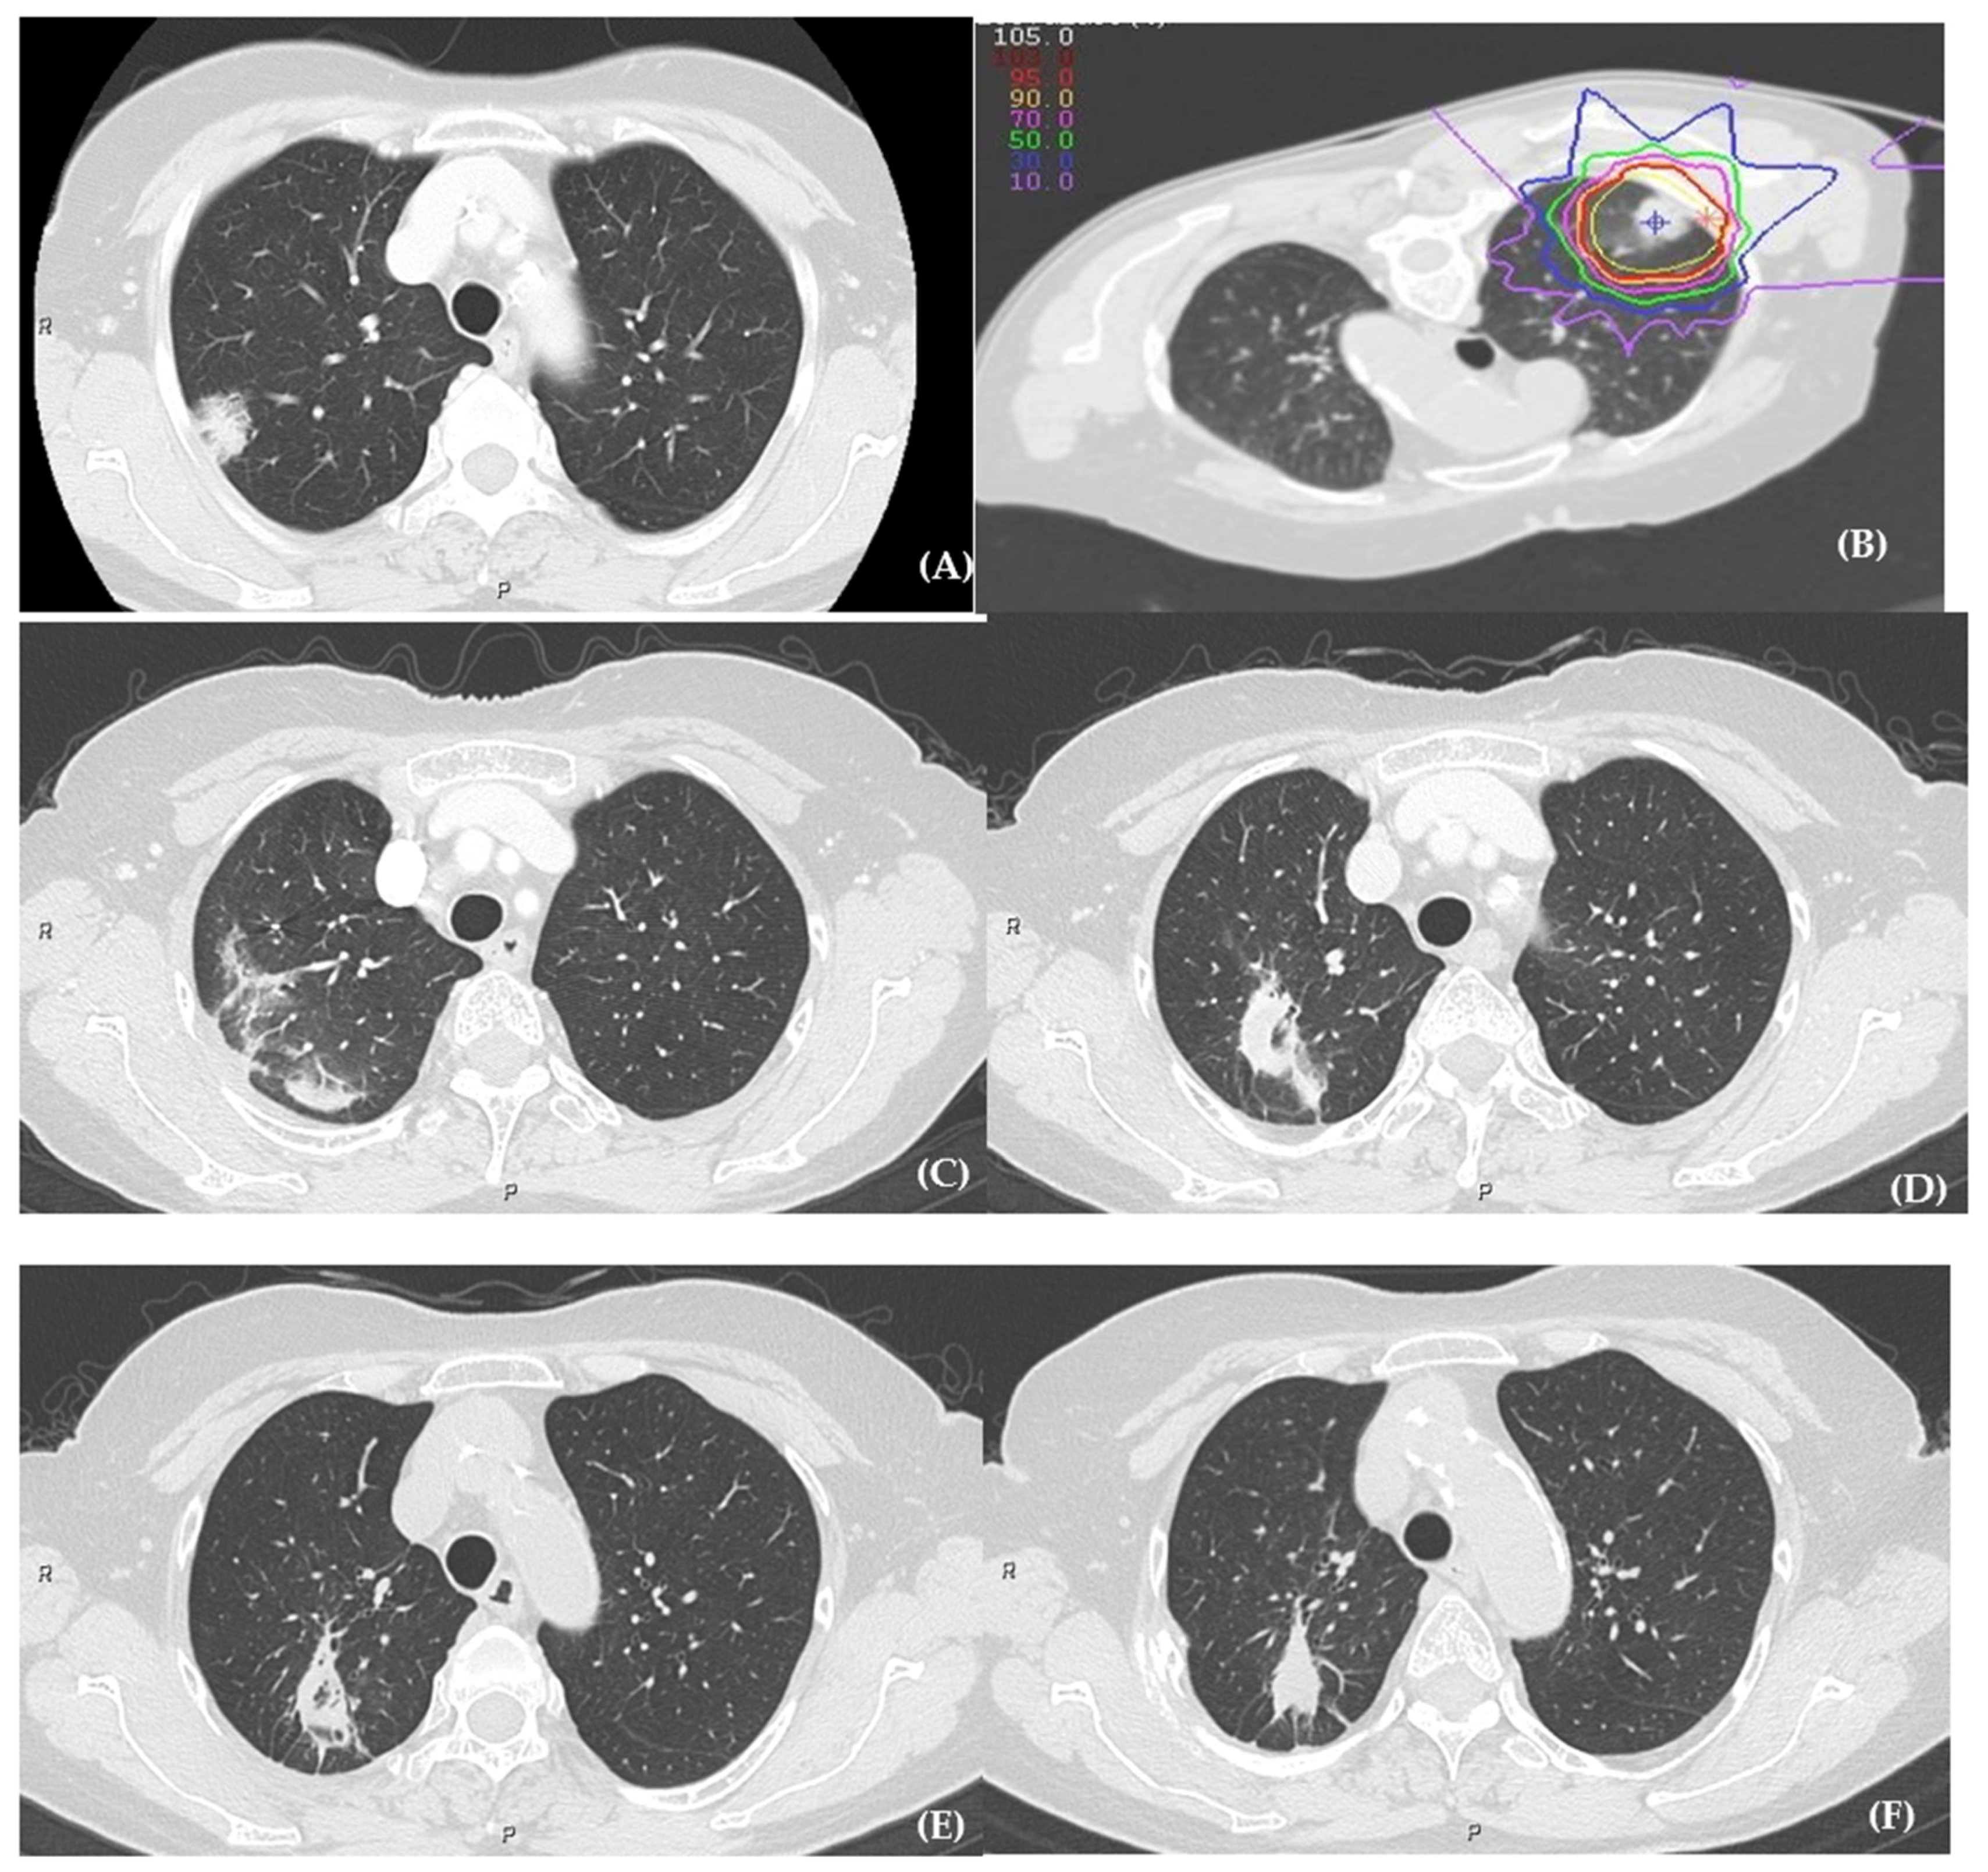

3.2. Radiation Pneumonitis

3.3. Correlation between Pretreatment Clinical Factors and Radiation Pneumonitis